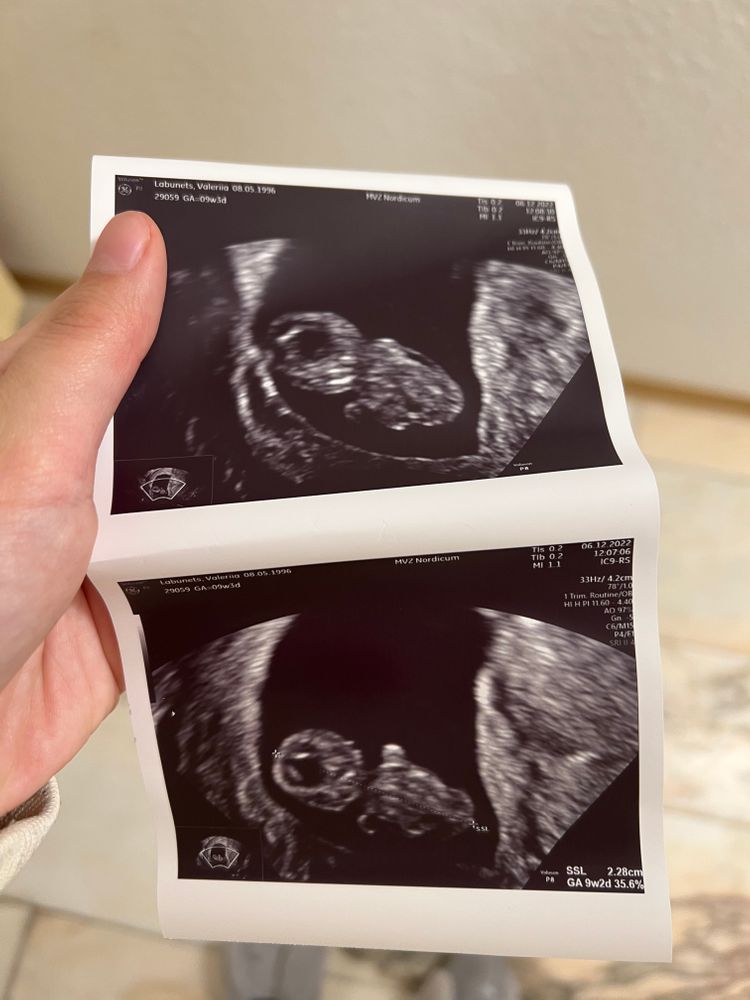

Как только узнала о беременности была на 7 небе от счастья❤️как сейчас помню пошла к врачу и на узи показало маленькое пятнышко 5 недель и 2 дня🙏🏻врач сказал прийти на 9 недели чтобы убедиться,что есть сердцебиение у малыша 👌но как только узнала о беременности начался через пару дней жуткий ТОКСИКОЗ 🥹боже это было ужасно с кровати встать не возможно ,от всего воротит ,голова кругом ,давление падает ,слабость ужасная не хотелось ничего 😭еле я дотянула до 9 недели пришла к врачу еле залезла на кресло всё крутилось вокруг и вдруг на экране маленькое чудо мой малыш ,моё счастье его сердечко так сильно билось💕я была счастлива 🥰вышла от врача я окрыленная но мой дорогой друг токсикоз был со мной и ни как не хотел меня покидать ☹️слава богу приехала моя любимая мамочка 🥹😘и окружила меня любовью и заботой 👌я вообще не вставала у меня начались плюс ко всему ужасные мигрени в добавок с рвотой настолько сильные были головные боли ничего не помогало ☹️на 10 недели и 2 днях у меня пошли кровянистые выделения мы срочно поехали в госпиталь первый который был у нас по дороге вышла не довольный врач и сказала ,а что вы приехали у вас что прям по ногам течет даже если у вас и будет выкидыш мы вам ни чем не поможем 👍хотя у меня уже был выкидыш я знаю ,что это такое!хочу сказать я не знаю как я сдержалась и не высказала ей все что о ней думаю😆я промолчала она сделала узи сказала плод на месте и отправила меня домой 🏠я решила себя не накручивать,а мама сказала все в руках бога не нервничай все будет хорошо выделений не много…мы приехали домой я легла и к утру ничего уже не было👍и тут пришла 13 неделя и о Боги токсикоз решил отступить я была на 7 небе от СЧАСТЬЯ ‼️Думаю чуть позже продолжу историю😂👌как говорится продолжение следует 🥹